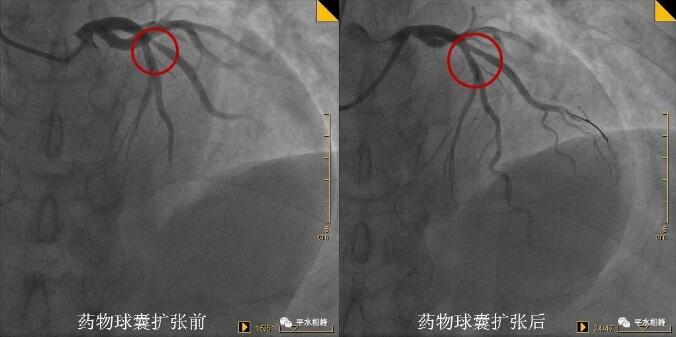

病例一 53岁中年男性,胸闷不适1月入院。1年前曾行支架植入术,复查冠脉造影提示支架内再狭窄。于支架内行药物球囊扩张术,术后效果良好。 病例二 69岁老年男性,突发胸痛1.5小时入院。既往有高血压、糖尿病病史。反复冠脉造影提示回旋支开口较前狭窄加重,行药物球囊扩张术,术后未再发作胸痛。 病例三 53岁中年男性,发作性胸部不适1月入院。新发现高血压、糖尿病。冠脉造影提示第一对角支粗大,开口狭窄80%,行药物球囊扩张术,术后效果良好。 什么是药物球囊扩张术 据高希春主任医师介绍,药物涂层球囊(DCB),是在传统球囊上基础上,均匀地涂上紫杉醇和造影剂(碘普罗胺)的混合基质,医生用30~45秒的时间扩张球囊,把药物贴粘至心脏冠状动脉的病变部位,起抗细胞增殖的作用,然后球囊和导管撤出体外,患者体内不留任何异物。 与目前治疗冠心病的主要临床手段--药物支架相比,药物球囊具有显著优势: ①在完成对病变血管的治疗后撤出体外,不留在人体内,能大大减轻血管内膜炎症反应,同时有效维持血管正常解剖结构,为患者保留必要的后续治疗机会。 ②没有支架的Polymer聚合物基质,同时无金属网格残留,在人体内不留异物,可明显减少血栓发生率,可将患者服用双联抗血小板凝聚药物的时间由药物支架的12个月以上缩短到1~3个月,可极大地降低患者出血的风险。 但并不是所有患者适合药物球囊,药物球囊主要适用于某些分叉病变、支架内再狭窄、小血管病变、弥漫性病变等药物支架疗效不佳或无法治疗患者。 药物球囊扩张技术以前只能在三甲及以上医院开展。随着药物涂层球囊技术在我院的开展,避免了患者必须转诊至市级以上大医院才能完成该手术的困境。 【科室简介】 心内科二病区目前共有医护人员23人,其中主任医师1名,副主任医师2名,主治医师6名,住院医师1名,其中硕士学历6人。科室擅长冠心病及其介入诊疗,心律失常及永久起搏器植入术,心内科常见疑难危重病例的诊治。 医院心内科介入团队2018年共完成冠脉造影+支架植入术1600多例,急诊PCI近二百例,均取得良好效果。 心内科二病区位于住院部五楼西区 护士站电话:0533-8228195 医生办公室:0533-822882